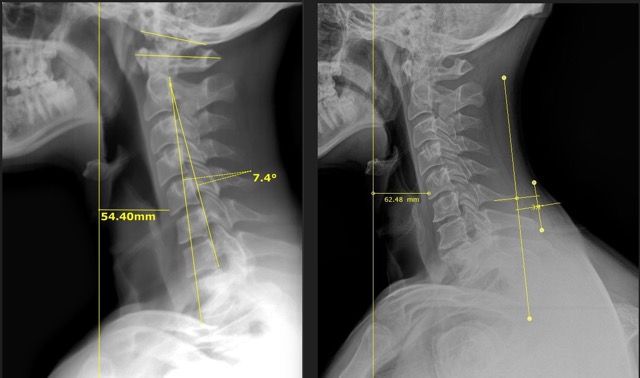

We use detailed X-rays to measure the exact position of your head in relation to your spine. This gives us a clear starting point and allows us to track your improvement with objective measurements.

We take follow-up X-rays to show you exactly how your spine is changing. The images don't lie - you'll see real structural improvement, not just temporary relief.

Our before and after X-rays show dramatic improvements in neck curve and head positioning. What many people think is a permanent problem can actually change with the right care.